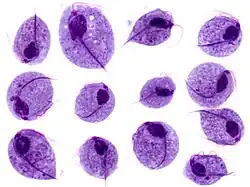

| Trichomonas-trofozoïten | |||||||||

Trichomonas is een geslacht van protista. Besmetting met Trichomonas vaginalis wordt ook wel kortweg trichomonas genoemd in plaats van trichomoniasis. Wereldwijd is trichomonas de meest voorkomende niet-virale geslachtsziekte. In Nederland worden zo'n 2000 besmettingen per jaar geconstateerd.

Bij onderzoek van het uitstrijkje (cervixcytologie) is de Trichomas vaginalis de meest voorkomende parasiet. De incubatietijd van trichomonas ligt tussen de 4 en 28 dagen. Hij kan abnormale vaginale afscheiding (fluor vaginalis) veroorzaken maar is niet altijd pathogeen.

In ongeveer 10-20% geeft hij een infectie van de lagere urinewegen, gepaard met dysurie. Bij 10-25% van de patiënten zien we een vies ruikende groengele, schuimige vaginale afscheiding, vaginale jeuk en vaginaal bloedverlies. Symptomen als PID (Pelvic Inflammatory Disease)en inguinale lymphadenopathie (vergrote lymfeklieren) kunnen voorkomen.

Trofozoït van Trichomonas vaginalis -